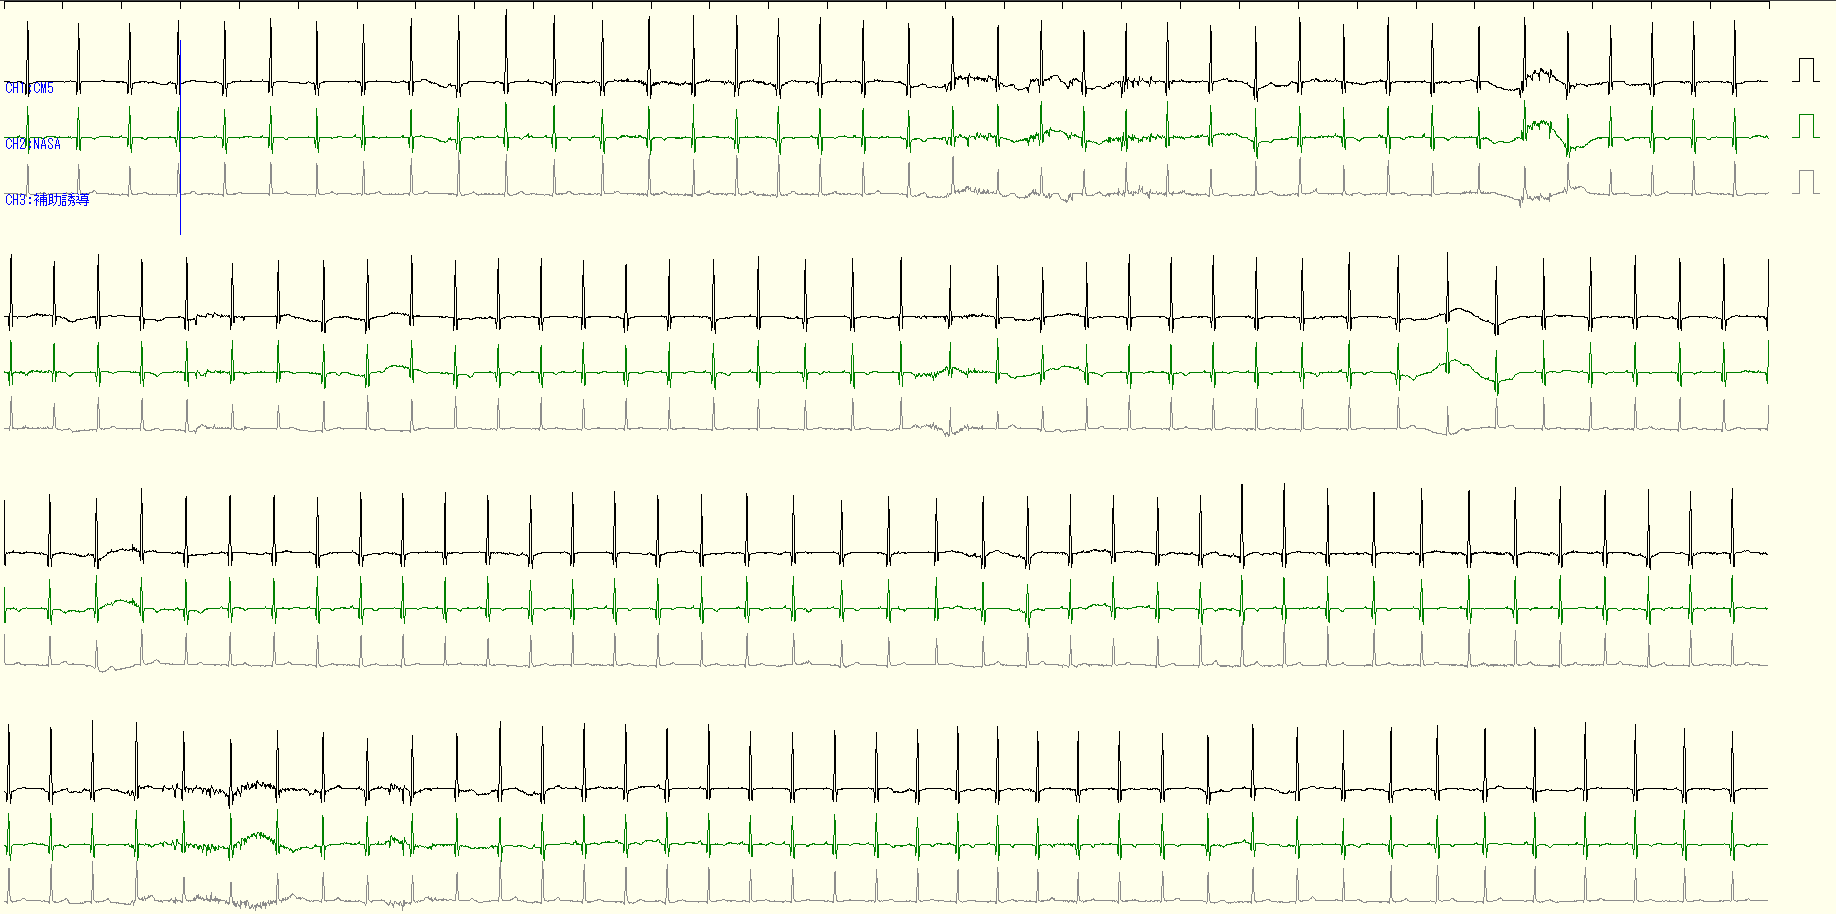

心電図(ECG)のR-R間隔変動をパワースペクトル解析し、自律神経活動(交感神経・副交感神経)のバランスを推定します。これにより、ストレスや疲労などの生体状態を非侵襲で客観的に評価できます。

人間の心拍は、1日に平均して約10万回打ちます。この波形から疾患早期スクリーニングの指標を構築したり、環境がヒトの生体に及ぼす影響を研究するビッグデータプロジェクト(データ駆動型研究)に取り組んんでいます。